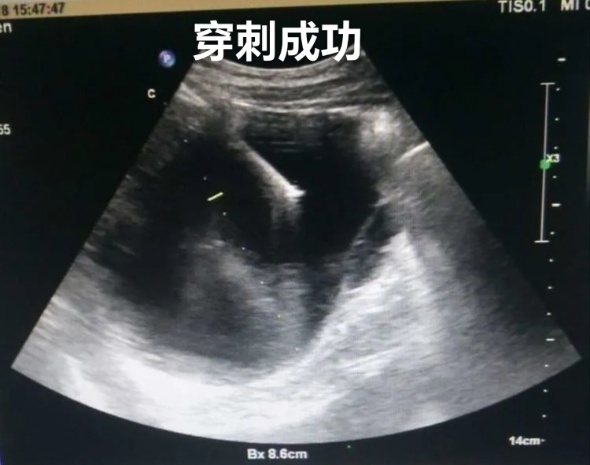

肝囊肿经皮超声引导性介入治疗

2、超声引导下囊肿抽液硬化治疗,肝囊肿、肾囊肿穿刺抽液硬化治疗,盆腔囊肿穿刺抽液硬化治疗,甲状腺、乳腺囊肿穿刺抽液治疗。

3、超声引导下置管引流,胸腹水穿刺及置管引流、心包积液穿刺置管引流、脓肿穿刺置管引流。